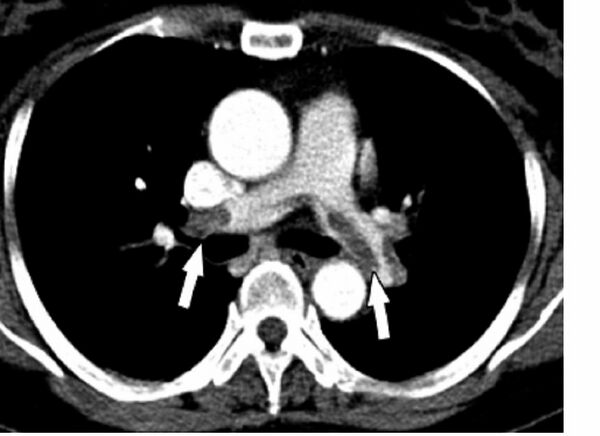

КТ-ангиопульмонография позволяет обнаружить тромбы в лёгочной артерии. При данном методе датчик вращается вокруг больного, которому предварительно вводится внутривенно контрастный препарат. В результате создаётся объёмная картина лёгких. Однако пациент должен суметь задержать дыхание во время процедуры (несколько секунд). Метод менее инвазивен и более безопасен, чем ангиография[10]. По мнению экспертов Европейского общества кардиологов у больных высокого риска достаточно однодетекторной КТ для подтверждения или исключения ТЭЛА. У больных невысокого риска рекомендуют мультидетекторную КТ, так как она позволяет более чётко выявить тромбы в ветвях лёгочной артерии[18].